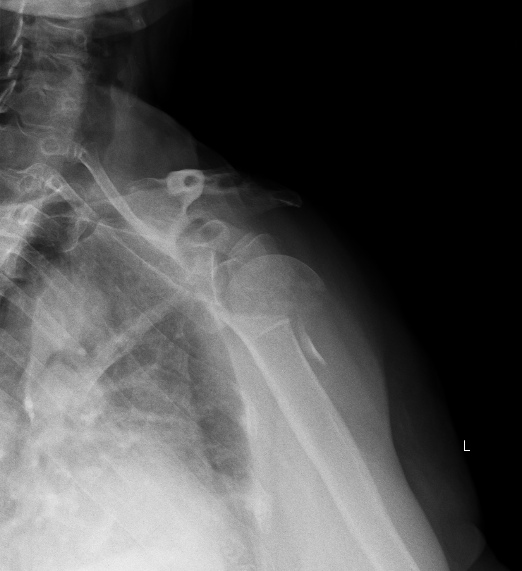

Да что Вы такое говорите, Юрий Алексеевич! Это самый что ни на есть махровый четырехфрагментный перелом, то есть анатомическая шейка плюс оба бугорка. Головка, можно считать, в вывихе, так что это ближе к 11-C3.2(2).

Анатолий Федорович, дорогой - чего там не видно на одном фасном снимкке, без КТ даже? Перелом по анатомической шейке виден? Бугорки отломленные видно? То, что суставная поверхность кнаружи-книзу смотрит, то есть вывихнута, видно?

Остеосинтез можно сделать хоть спицами, но надо в любом случае открываться, и не только вправить головку, но и фиксировать бугорки к плечу, то есть сухожилия прошить хорошо. В приложении картинки с аналогичным переломом.

согласен, перелом 4-х фрагментарный, при такой картинке, учитывая возраст, оптимальнее будет гемипротез.

Действительно данный перелом 4-х фрагментарный с вывихом головки плеча. При таком переломе,скорее всего,предпочтение надо отдать гемиартропластике.